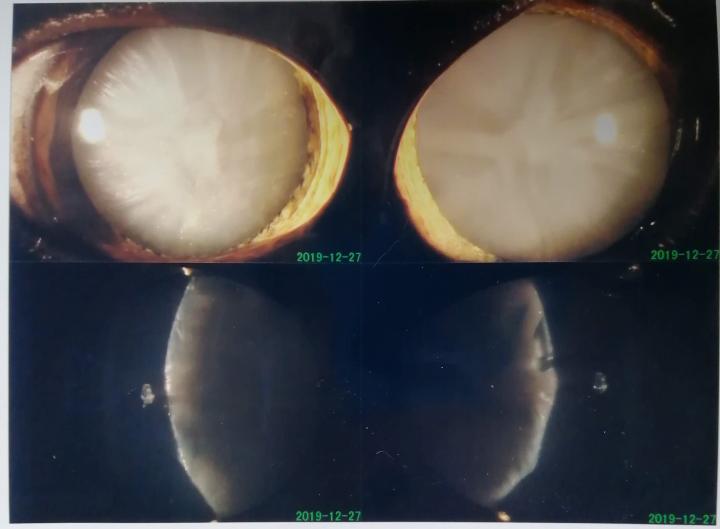

12月末のナイルの眼 過熟白内障

過熟白内障(ステージ4)でも手術可能

白内障の程度

ステージ4.過熟